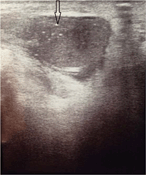

Thoracic outlet syndrome as a consequence of isolated atraumatic first rib fracture

Aleem K. Mirza and Audra A. Duncan

Journal of Surgical Case Reports, Volume 2017, Issue 6, June 2017, rjx100, https://doi.org/10.1093/jscr/rjx100